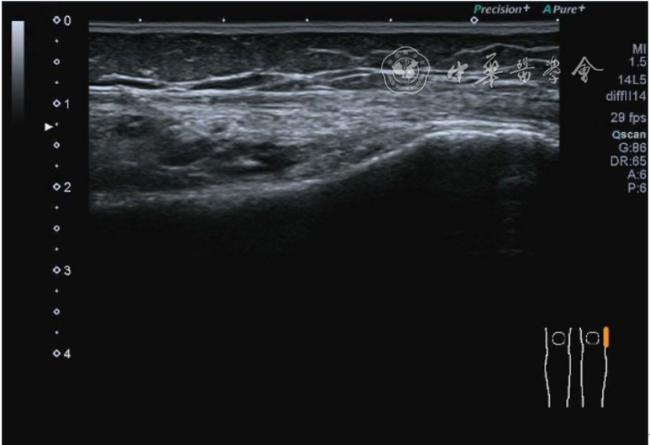

1.髂胫束局部治疗。仍以保守治疗为首选。如物理治疗、口服药物、康复训练等,早期可以超声引导下肌腱表面注射治疗。针刀剥离松解治疗具有创伤小、恢复时间短、感染率低、适应证广,无绝对禁忌证等优势,可作为首选手术方案。(1)髂胫束胫骨附着点表面局部药物注射治疗。患者侧卧位,髋内旋,膝关节屈曲20°~30°,膝下垫枕。局部消毒,铺无菌巾,穿刺区域常规消毒,探头涂抹耦合剂后套入无菌手套碘伏消毒或使用无菌耦合剂,长轴显示髂胫束,找到胫骨附着点病变部位。选用25G针头,抽取1%利多卡因3 ml+曲安奈德10 mg,超声引导下针尖到达肌腱表面进行注射(图28),注射完毕拔出针头,局部压迫2分钟,穿刺点创可贴覆盖。(2)髂胫束股骨外髁附着点局部药物注射治疗。体位及治疗前准备同髂胫束胫骨附着点表面局部药物注射治疗,长轴显示髂胫束,找到股骨外髁附着点病变部位。确定髂胫束与股骨外髁之间为靶点,选用25G针头,抽取1%利多卡因3 ml+曲安奈德10 mg,超声引导下,针尖到达骨表面进行注射(图29),注射完毕拔出针头,局部压迫2分钟,穿刺点创可贴覆盖。(3)髂胫束胫骨附着点局部针刀剥离松解治疗。体位及治疗前准备同髂胫束胫骨附着点表面局部药物注射治疗。超声探头长轴位扫查,根据压痛点和超声显示肌腱变化的位置确定靶点。用1%利多卡因3 ml沿韧带表面及胫骨止点病变部位局部麻醉。选用直径0.6 mm的Ⅰ型2号针刀由近端向远端平面内进刀,平刀在韧带表面剥离松解3~5刀,然后进入胫骨附着点损伤处进行剥离松解3~4刀拔出针刀(图30),局部压迫止血5分钟,无菌敷料覆盖。(4)髂胫束股骨外髁附着点局部针刀剥离松解治疗。体位及治疗前准备同髂胫束胫骨附着点表面局部药物注射治疗。超声探头长轴位扫查,根据压痛点和超声显示肌腱变化的位置确定靶点。用1%利多卡因3 ml沿股骨外髁部位的髂胫束表面局部麻醉。选用直径0.6 mm的Ⅰ型2号针刀由近端向远端平面内进刀,平刀在髂胫束表面剥离松解3~5刀拔出针刀(图31),局部压迫止血5分钟,无菌敷料覆盖。

图29 超声引导下髂胫束股骨外髁附着点局部药物注射治疗